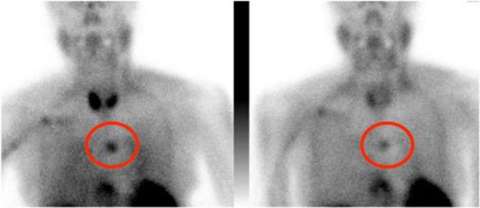

The older of the two tests is the parathyroid scan, also known as a nuclear medicine scan or sestamibi. In this test, you are injected with a chemical that the parathyroid glands take up more than the rest of your body. The problem with this test is that the pictures are very fuzzy, and you can only tell the basic area of where the parathyroid glands are. This is why sometimes a nuclear medicine scan is done together with a CT scan to make it a little bit more precise.

Nuclear Medicine Scan or Sestamibi